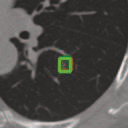

Deep learning based medical image segmentation models usually require large datasets with high-quality dense segmentations to train, which are very time-consuming and expensive to prepare. One way to tackle this challenge is by using the mixed-supervised learning framework, in which only a part of data is densely annotated with segmentation label and the rest is weakly labeled with bounding boxes. The model is trained jointly in a multi-task learning setting. In this paper, we propose Mixed-Supervised Dual-Network (MSDN), a novel architecture which consists of two separate networks for the detection and segmentation tasks respectively, and a series of connection modules between the layers of the two networks. These connection modules are used to transfer useful information from the auxiliary detection task to help the segmentation task. We propose to use a recent technique called "Squeeze and Excitation" in the connection module to boost the transfer. We conduct experiments on two medical image segmentation datasets. The proposed MSDN model outperforms multiple baselines.